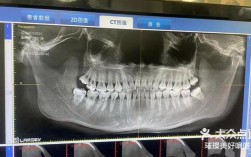

| 治疗步骤 | 初诊检查:口内检查、制取研究模型、拍摄X光片(全景片、头颅侧位片); 方案设计:结合影像资料制定个性化方案,可能涉及拔牙、骨钉植入、邻面去釉等; 矫治器粘接/佩戴:分次粘接托槽或领取隐形矫治器; 定期复诊:每4-6周调整一次(固定矫治器)或每1-2周更换一副隐形矫治器; 拆除矫治器:达到目标后拆除,佩戴保持器 |